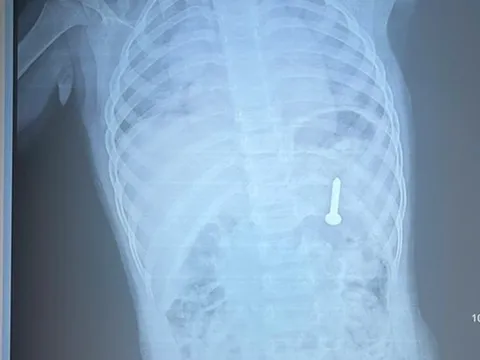

Đau bụng đi khám, người đàn ông "sốc" phát hiện bàn chải nằm trong bụng 52 năm

Nuốt phải bàn chải từ năm 12 tuổi nhưng giấu gia đình vì sợ bị mắng, nhầm tưởng vật thể sẽ tự phân hủy theo thời gian nhưng không ngờ đên khi 64 tuổi người đàn ông "sốc" khi biết dị vật vẫn nguyên vẹn trong bụng.